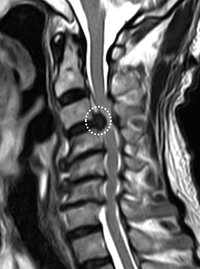

これらの症状に加え、首を後ろに反らしたり、痛い方に傾けたりすると上肢の痛みやしびれが増強します。医師はこうした症状を基に、上肢の知覚や筋力などを調べてこの疾患を疑い、画像検査を行います。画像検査は通常の頸椎単純エックス線写真に加えてMRI検査を行います=画像=。MRIで椎間板の明らかな突出を認めた場合は容易に診断できますが、椎間板の突出が軽度な場合には診察所見と画像検査所見とを照らし合わせて診断します。